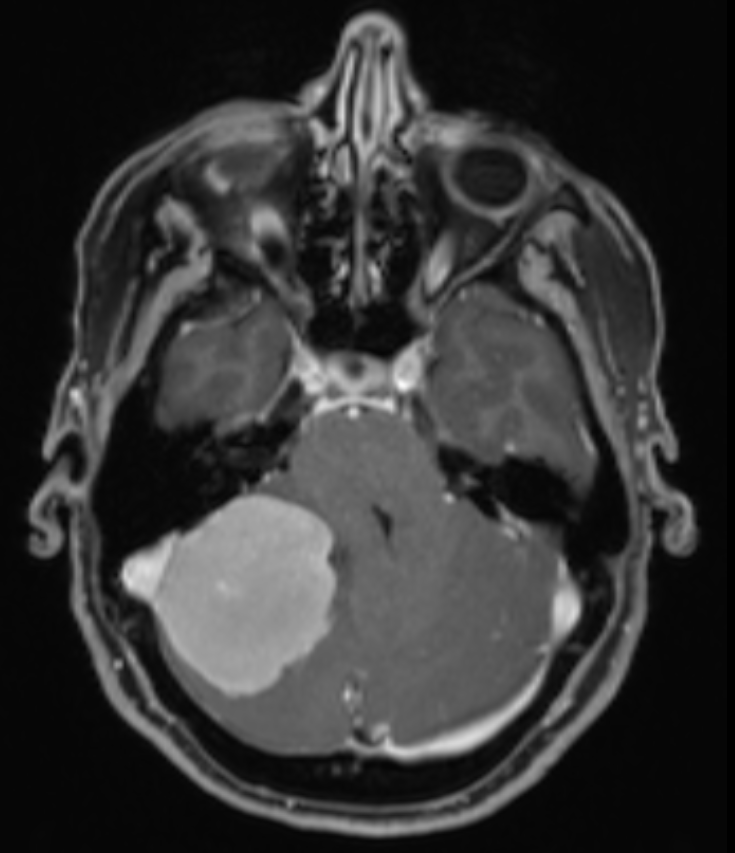

Bildgebung

Kleinhirnbrückenwinkel Meningeom MRI

MRI eines Meningeoms im Kleinhirnbrückenwinkel auf der rechten Seite.